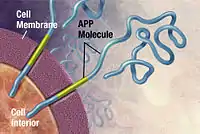

Alzheimer's disease has been identified as a protein misfolding disease, a proteopathy, caused by the accumulation of abnormally folded amyloid beta protein into amyloid plaques, and tau protein into neurofibrillary tangles in the brain.[93] Plaques are made up of small peptides, 39–43 amino acids in length, called amyloid beta (Aβ). Amyloid beta is a fragment from the larger amyloid-beta precursor protein (APP) a transmembrane protein that penetrates the neuron's membrane. APP is critical to neuron growth, survival, and post-injury repair.[94][95] In Alzheimer's disease, gamma secretase and beta secretase act together in a proteolytic process which causes APP to be divided into smaller fragments.[96] One of these fragments gives rise to fibrils of amyloid beta, which then form clumps that deposit outside neurons in dense formations known as amyloid plaques.[88][97]